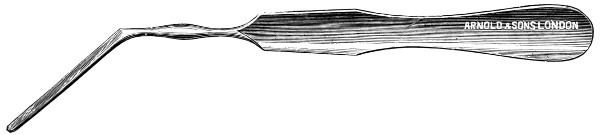

Fig. 11. Horsley’s Disk or Bone Elevator.

Fig. 12. Horsley’s Dural Separator.